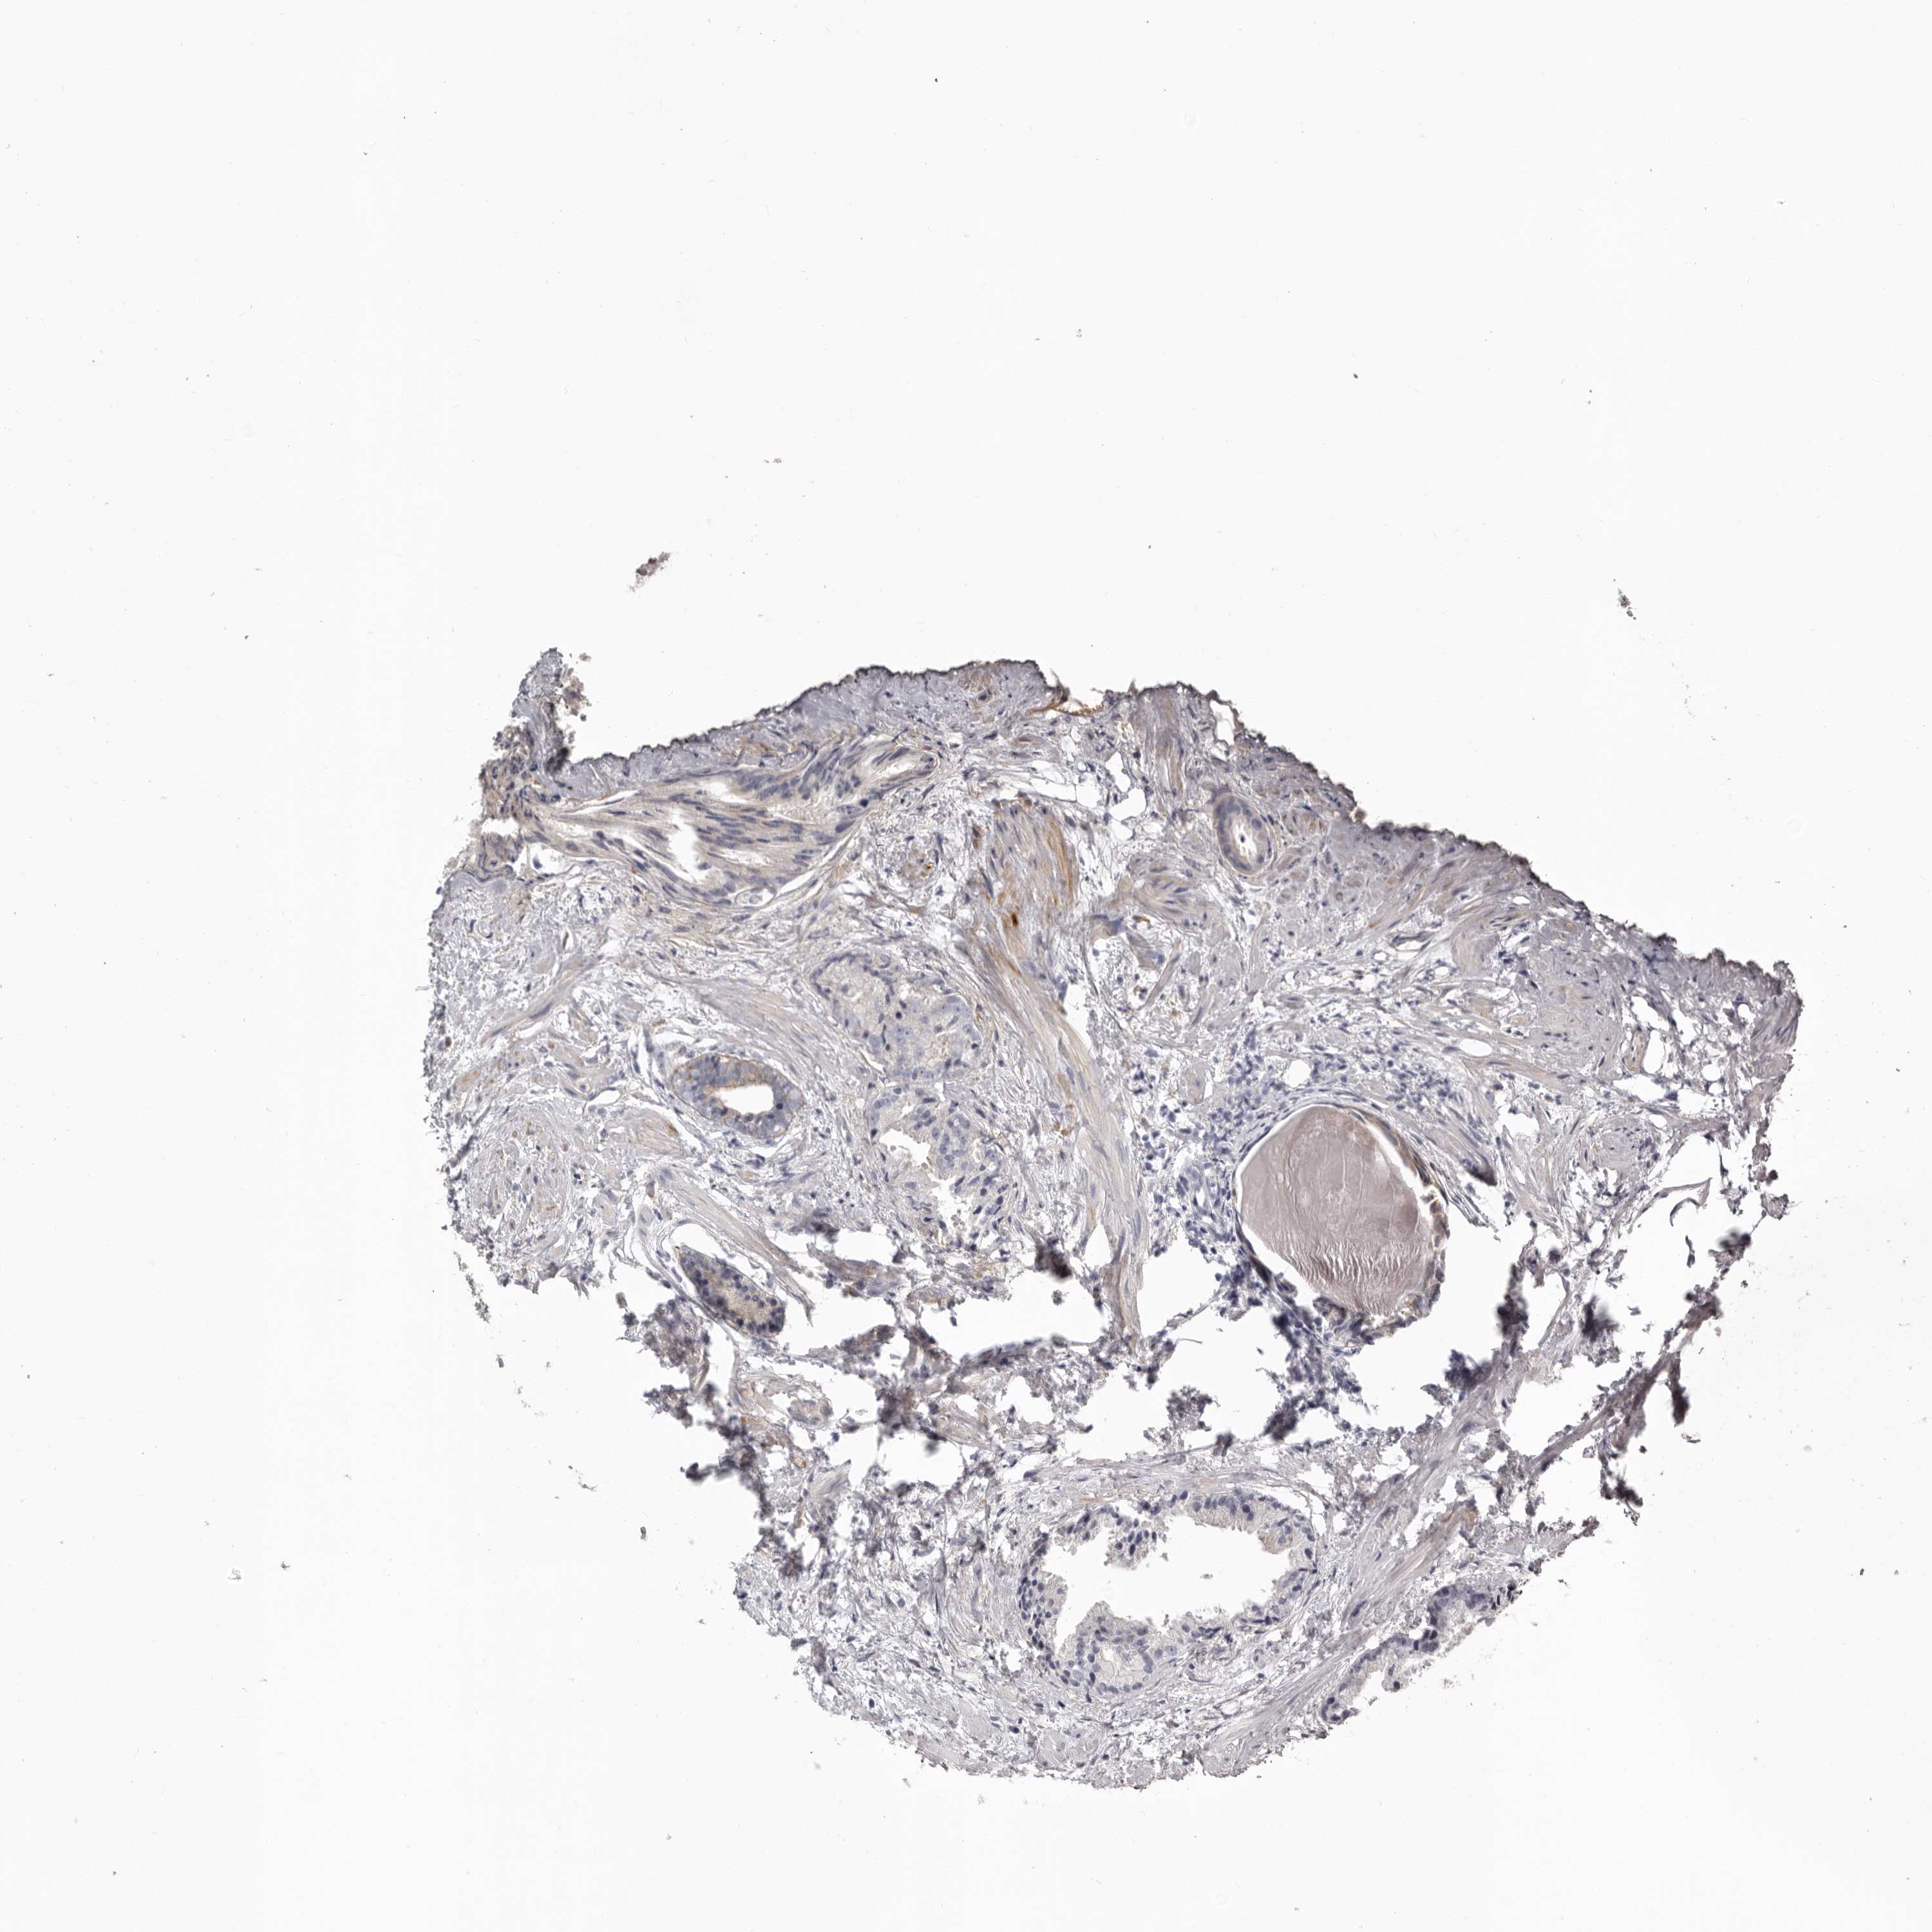

PROSTATE CANCER - Protein expressioni

A mouse-over function shows sample information and annotation data. Click on an image to view it in a full screen mode. Samples can be filtered based on level of antibody staining by selecting one or several of the following categories: high, medium, low and not detected. The assay and annotation is described here.

Antibody stainingi

Antibody staining in the annotated cell types in the current human tissue is reported as not detected, low, medium, or high, based on conventional immunohistochemistry profiling in selected tissues. This score is based on the combination of the staining intensity and fraction of stained cells.

Each image is clickable and will lead to virtual microscopy that enables deeper exploration of all samples and also displays staining intensity scores, fraction scores and subcellular localization as well as patient and tissue information for each sample.

Antibody HPA028448

Antibody HPA028696

Staining

High

Medium

Low

Not detected

Intensity

Strong

Moderate

Weak

Negative

Quantity

>75%

75%-25%

<25%

None

Location

Nuclear

Cytoplasmic/membranous

Cytoplasmic/membranous,nuclear

Adenocarcinoma, High grade

Adenocarcinoma, Low grade

Adenocarcinoma, Medium grade